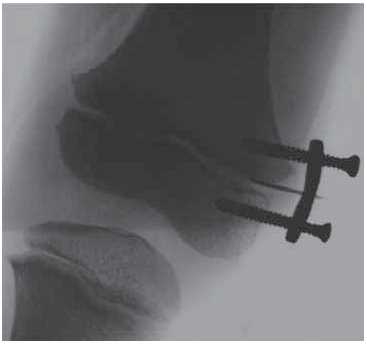

Surgical intervention was performed under general anesthesia. A linear 15-cm-long incision of the skin and subcutaneous tissue was made along the outer surface of the right thigh in the upper and middle third. A fibrous cord with a width of up to 1.5 cm, fused to the iliotibial tract and surrounding soft tissues with multiple scarring cords was isolated. The cord was isolated from the surrounding soft tissues. Right thigh adduction caused it to stretched, limiting the amplitude of movements in the right hip joint. Up to 15 cm of the cord was excised (Fig. 5). The wound was drained and sutured layer-by-layer. In addition, a tenotomy of subspinal muscles was performed through a 4-cm-long access channel along the anteroexternal surface of the proximal part of the right thigh, and the fibrous cords that limited abduction in the right hip joint were transected. The wound was drained and sutured layer-by-layer. The level of the distal growth zone of the right femur was determined under the control of the electronic optical transducer. Using a 2-cm-long access channel, the distal metaepiphyseal growth zone of the right femur was isolated and blocked using an 8-shaped plate with two screws inserted into the metaphyseal and epiphyseal sections of the bone (Fig. 6). The wound was sutured layer-by-layer. The right lower limb was fixed using an antirotation plaster cast. The postoperative period proceeded without complications. The wounds healed with primary tension and the pediatric patient was discharged from the hospital in a satisfactory condition.

Fig. 6. X-ray of the right knee joint at the stage of blocking the medial portion of the distal femoral growth zone with an eight-shaped plate